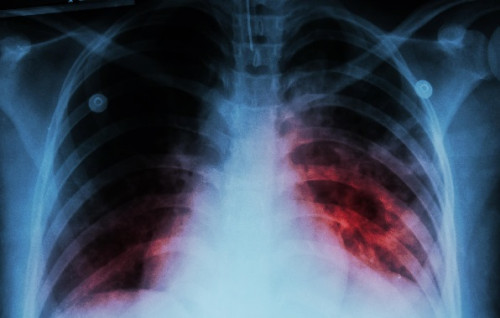

Aunque parece una enfermedad del pasado, la tuberculosis sigue cambiando vidas. Sus síntomas, su contagio y las causas que la mantienen activa preocupan.

Un estudio muestra que las cárceles de Paraguay son un entorno de alto riesgo para el desarrollo de la tuberculosis y que el riesgo continúa después de la liberación.

La Dirección General de Vigilancia de la Salud (DGVS) señaló que de 2.983 casos notificados en 2021, el 18% fue detectado en personas privadas de libertad, seguido de un 11% de la población indígena.